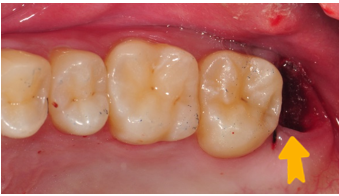

2.將智齒植入大臼齒位置,用鐵線固定

等待傷口恢復(約三個月)3.拆除固定鐵線、並將牙齒修型

4.裝上假牙,完成治療